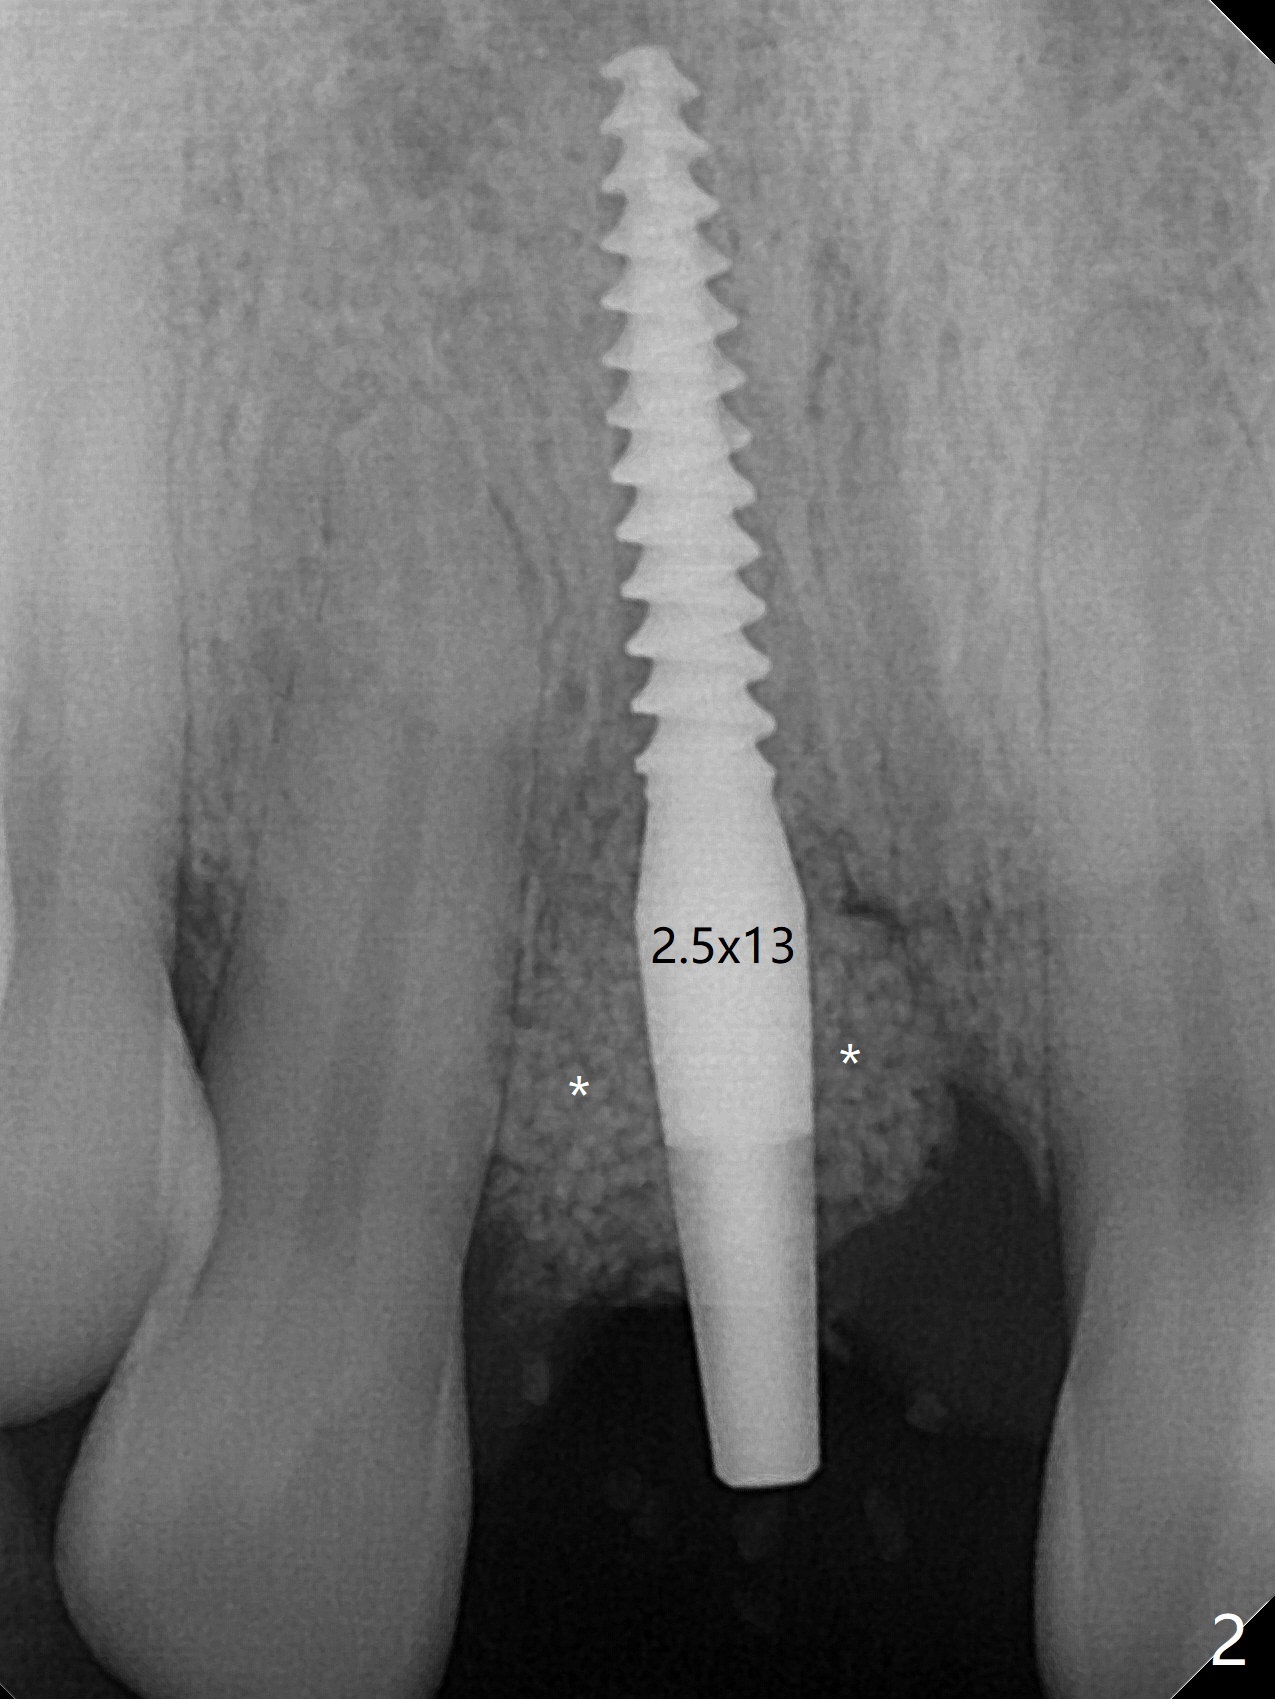

50岁女8号牙远中颊侧冠方移位(图一),牙根暴露(*),前磨牙-前磨牙开合,腭侧牙龈红肿。拔除清创后,使用导板钻洞,徒手植入2.5x13毫米一段式植体,首先将PRF膜插入腭侧,剩余牙槽窝空间植入粘性骨粉(图二:*)。截断拔除牙齿,牙冠掏空,反复调整牙冠长度,使用流动性树脂(flowable composite,图三:*)衬里固定牙冠(C),恰好PRF封闭远中颊侧牙槽窝开口(图四),自然牙冠和一段式植体配合,形成最佳emergency profile,最后牙周敷料进一步封闭牙槽窝(图五),防止骨粉早期脱落,不必担忧敷料不透气。腭侧牙龈红肿(图六)。服用Augmentin两天,患处没有触痛了(图七)。术后九天颊侧牙龈继续延长(图八).